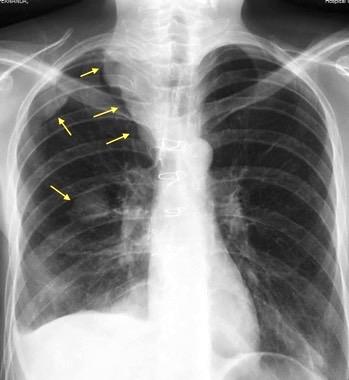

Tromboembolismo pulmonar.

Frecuencia del derrame:

Rx: 32%. TC: 47%

Unilateral. 85%

< 1/3 del hemitórax: 90%

Todos exudados

58% con eritrocitos

21% tabicación lo que causa demora en el diagnóstico

TEP. Empiema pleural. Atelectasia redonda

Porcel JM et al. Analysis of pleural effusions in acute pulmonary embolism: radiological and pleural fluid data from 230 patients. Respirology 2007/ Iguchi T et al. Desquamation of the subpleural lung parenchyma caused by empyema after pulmonary embolism: A case report. Respirol Case Rep. 2022 .

Derrame pleural 43-48% de pacientes con embolismo.

< 1/3 de hemitórax: 90%.(puede haber en lado opuesto).

Siempre exudados.

75% de los pacientes con TEP y derrame pleural tienen dolor pleurítico.

La disnea desproporcionada